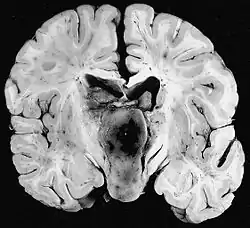

Macroscópicamente, el astrocitoma pilocítico suele presentarse como una masa quística bien definida, con un nódulo mural en la pared del quiste. Si es sólido, puede estar bien circunscrito o, con menos frecuencia, ser infiltrativo.

Microscópicamente, el tumor muestra un patrón bifásico, con células bipolares compactas de forma pilosa (de ahí su denominación "pilocítico") con largos procesos positivos para GFAP y zonas hipocelulares con microquistes. En las zonas sólidas, la neoplasia se compone de astrocitos neoplásicos con un citoplasma fibrilar intensamente eosinofílico y núcleos alargados y redondeados sin atipias. En las zonas microquísticas las prolongaciones citoplasmáticas tienen siempre la apariencia de fibrillas pero son menores en número y se irradian en todas direcciones. Son muy frecuentes en el astrocitoma pilocítico las fibras de Rosenthal[3][7] y los cuerpos granulares eosinofílicos. También puede haber proliferación vascular de aspecto glomeruloide no indicativa de malignidad.